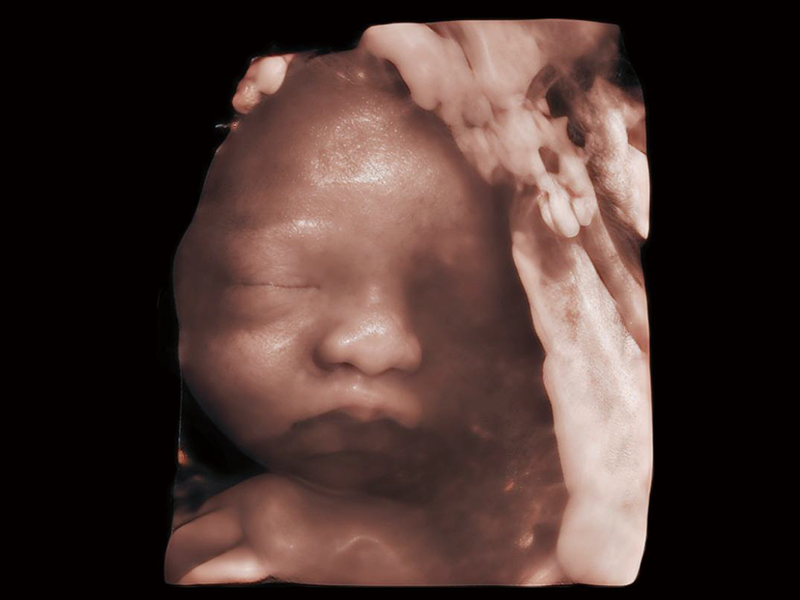

梦溪®P80以“关爱女性”为基石,提供全方位的解决方案,量身定制以满足女性的健康需求,涵盖妇科、生殖健康检查、产前筛查及产后康复等领域。